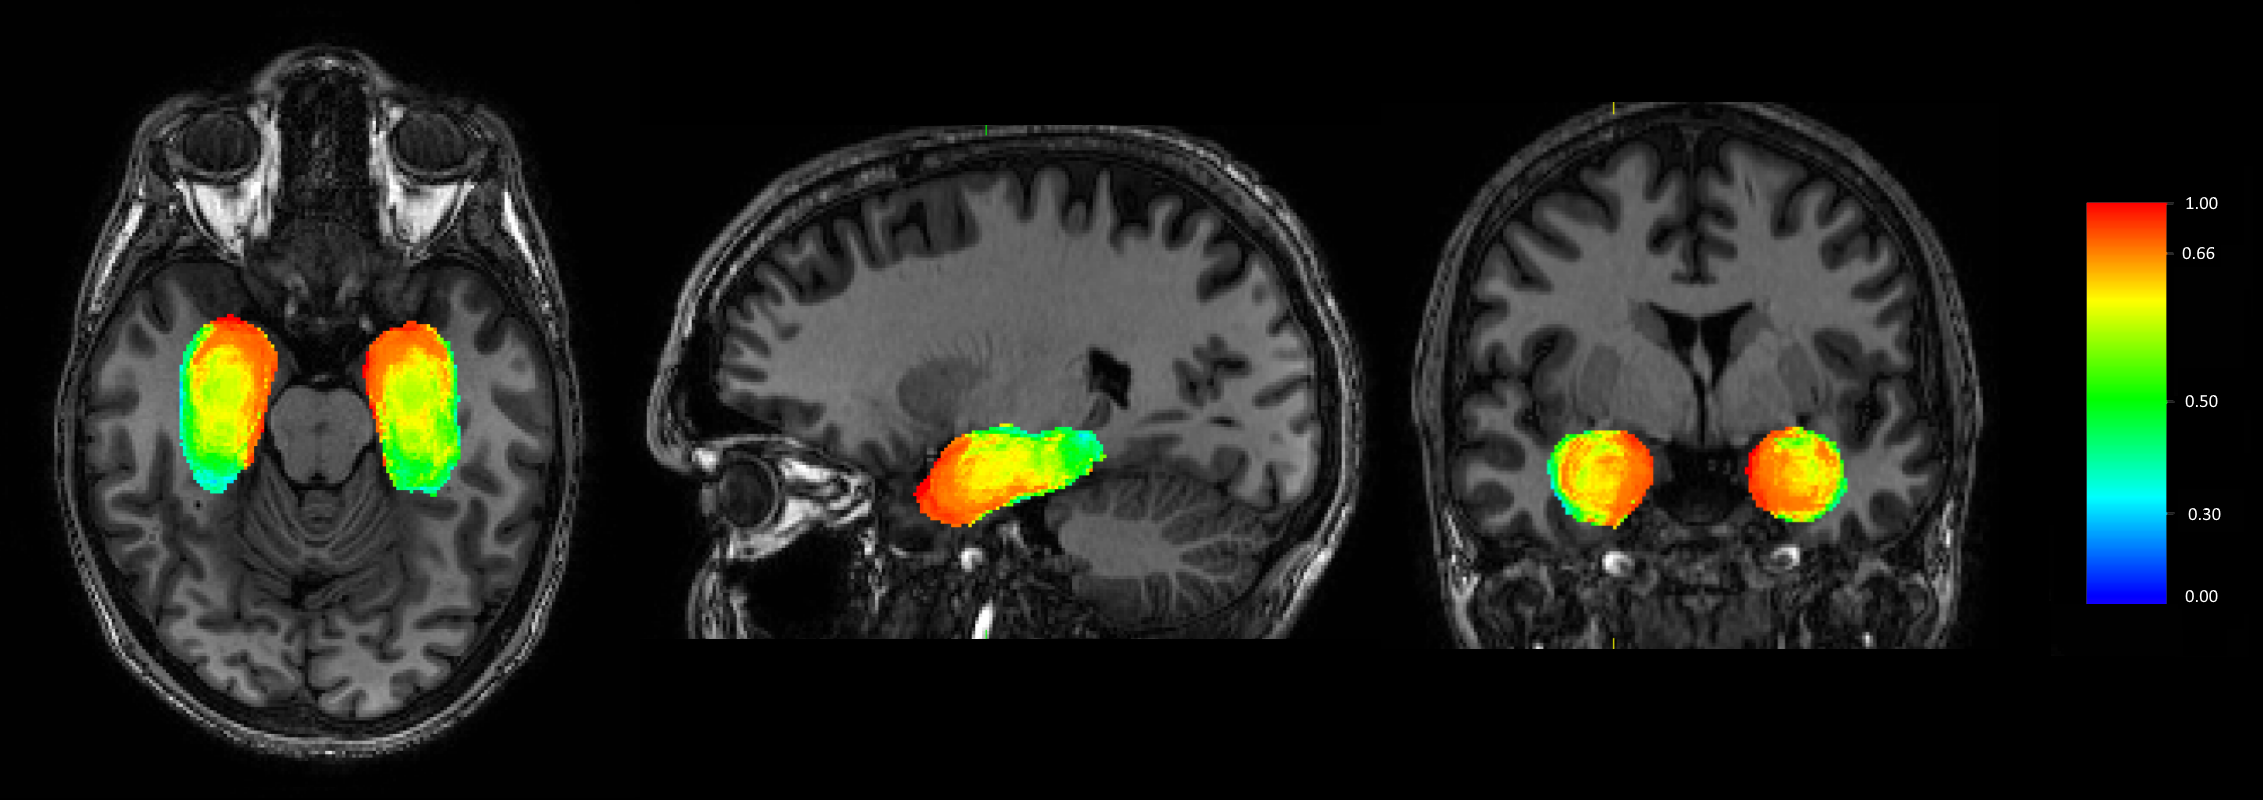

Segmentation of the Pulvinar in the Thalamus

The pulvinar of the thalamus is a higher-order thalamic nucleus that is responsible for gating information low to the cortical regions of the brain. Segmenting the pulvinar in clinically acquired images is important to support studies exploring its role in brain function.

In recent years, we have proposed an active shape model method to segment multiple thalamic nuclei, including the pulvinar. We validate the segmentation of the pulvinar using the known fact that the pulvinar has particularly strong white matter connections to the hippocampus, which allows us to identify the pulvinar from thalamic regions of high hippocampal structural connectivity.